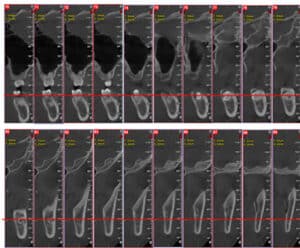

A Cone Beam CT is compiling 3D data, but it still allows us to access it only through 2d representations (slices) in a flat 2D screen. The surgeon has to read these combined 2D images and reconstruct a mental 3D structure of the surgical anatomy, certainly not an easy task to do with precision.

A Challenging surgical case with a complex of vertical and horizontal septa in the posterior sinus. Segmentation of the 3D radiographical and optical data and 3D printing in multiple layers from AMMA Ltd Hong Kong, has allowed for an accurate representation of the anatomy where multiple surgical access approaches were tested.